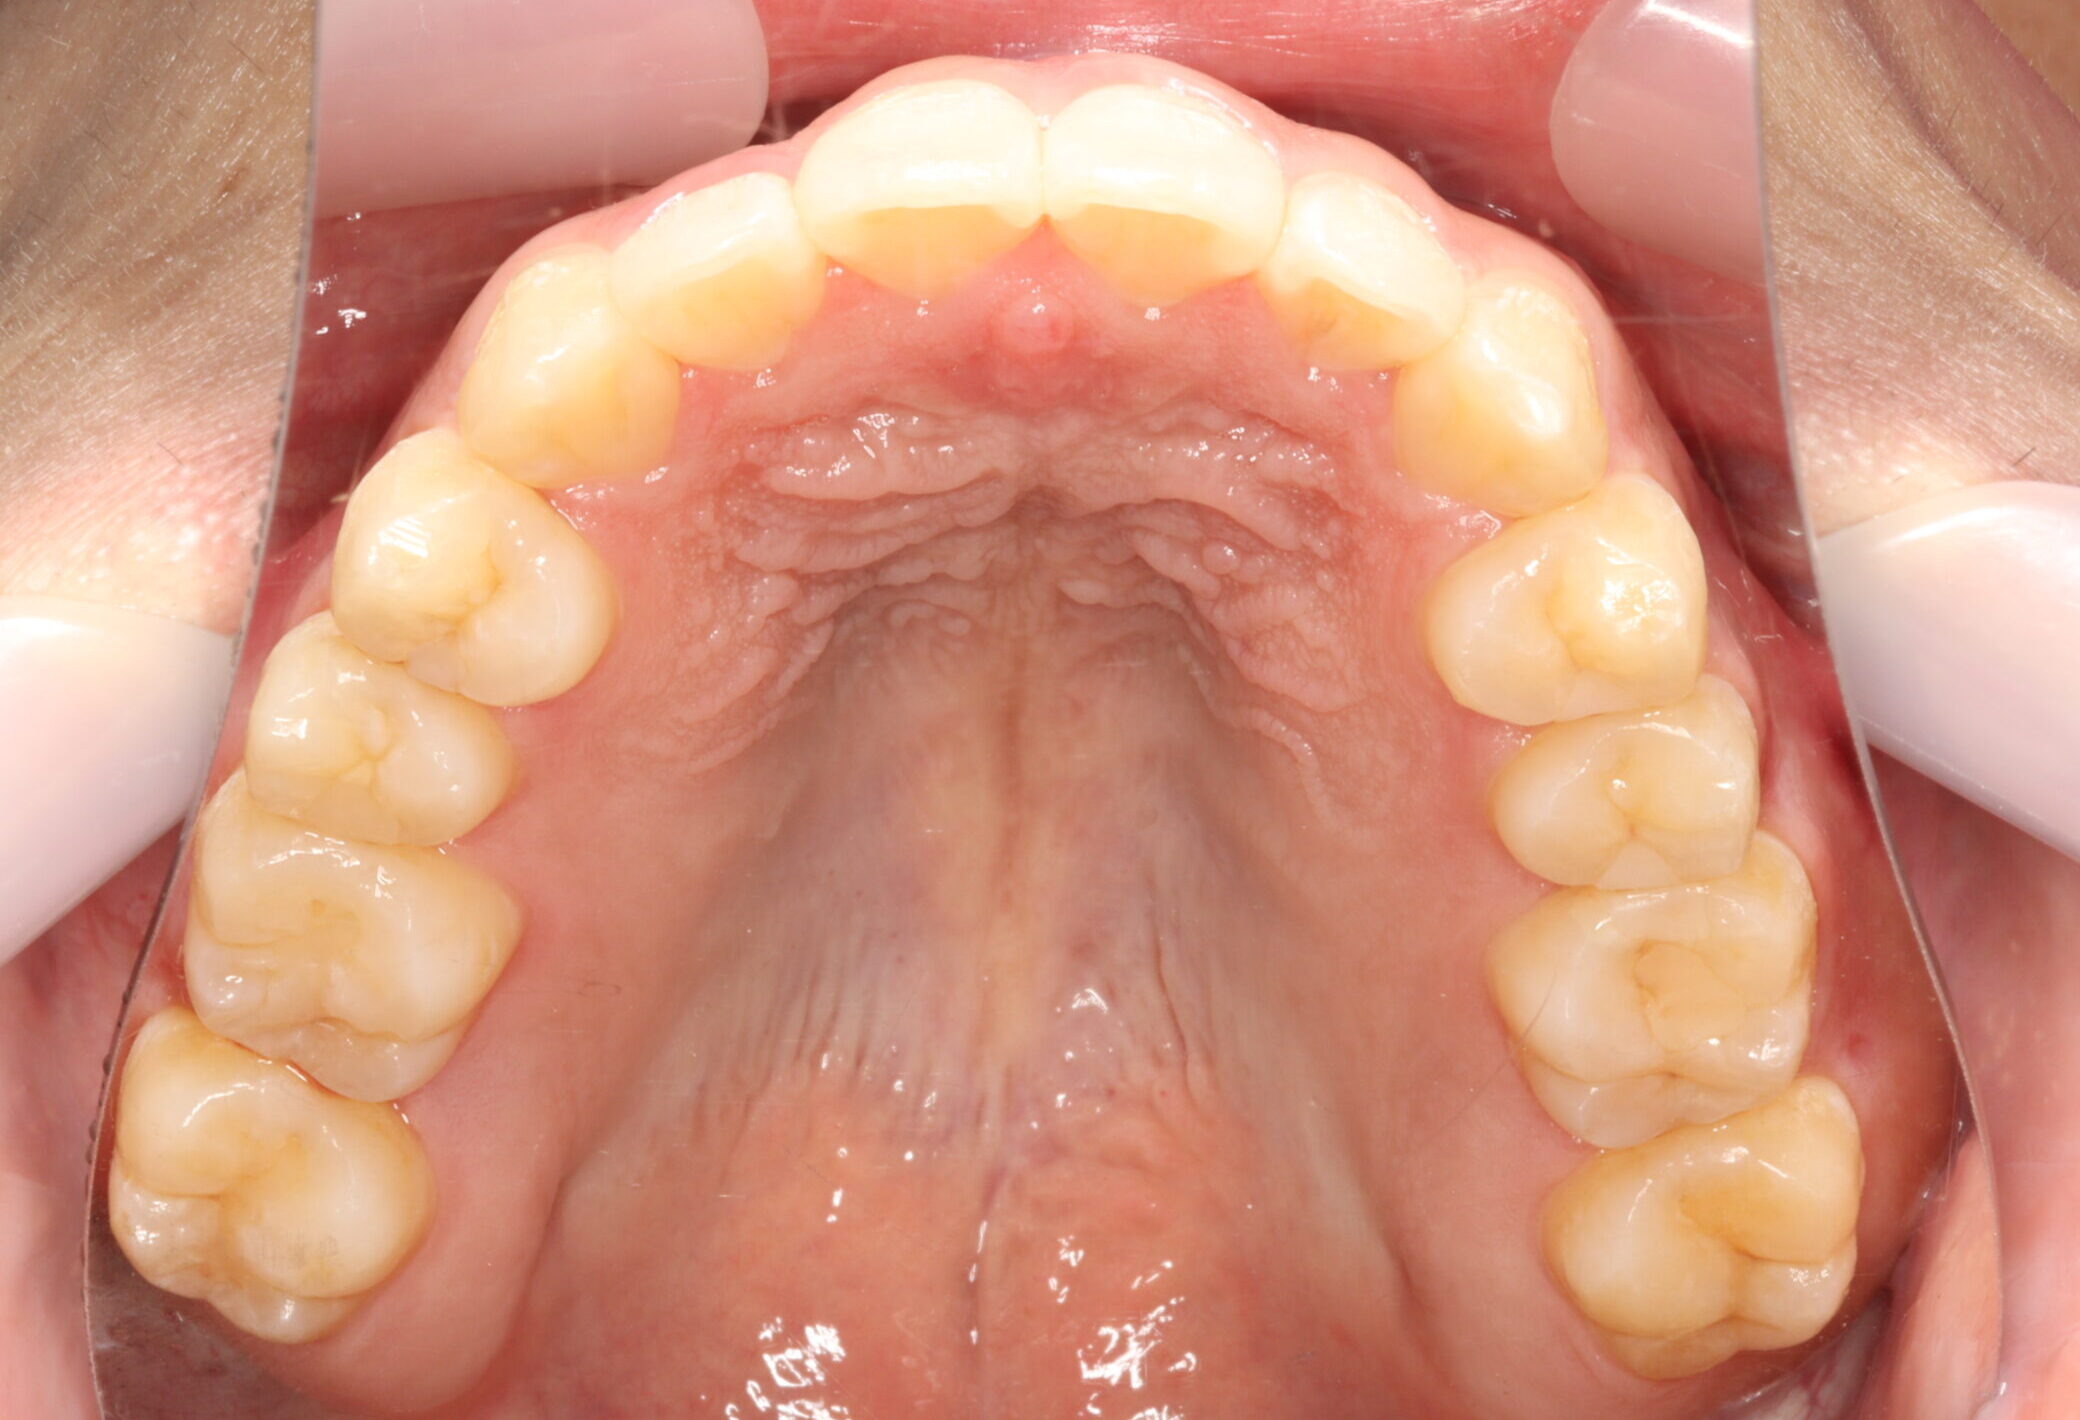

治療後

【診断】開咬、叢生(でこぼこ)、上下顎前歯唇側傾斜、舌突出癖

【治療方法】マルチブラケット装置にて排列を行う。咬合の確立のため顎間ゴムを併用し、舌突出癖の改善のため筋機能療法を行う